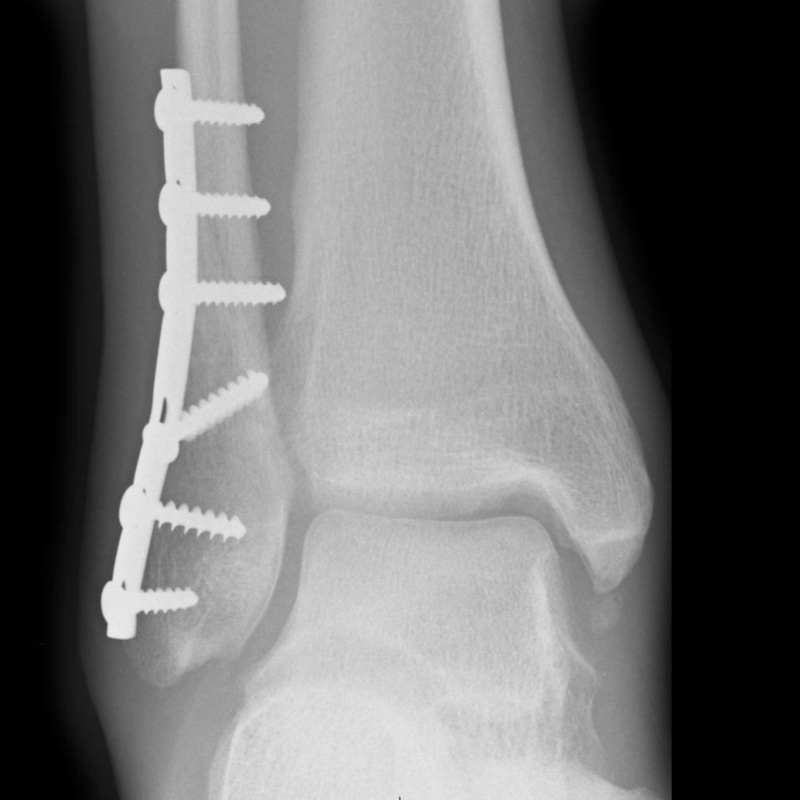

• Εσωτερική Σταθεροποίηση (Οστεοσύνθεση): Αυτή η μέθοδος περιλαμβάνει την τοποθέτηση μεταλλικών πλακών, βιδών ή ράβδων για να

σταθεροποιηθεί το κάταγμα εσωτερικά. Η ακριβής ευθυγράμμιση των οστών επιτρέπει την ταχύτερη και πιο σταθερή επούλωση.